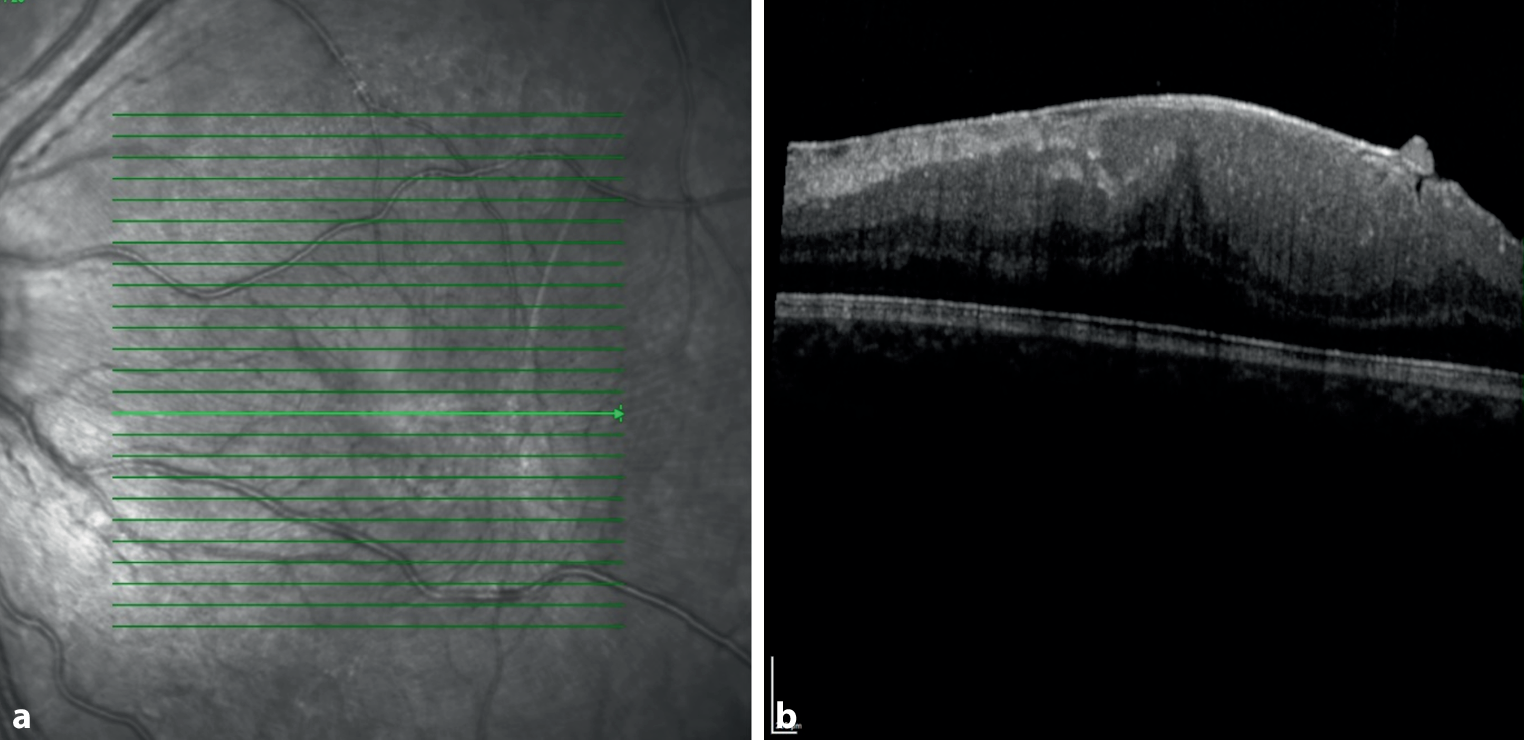

Das Makulaödem ist eine seltene, visusbedrohende Komplikation der juvenilen Uveitis. In einer retrospektiven Studie wird berichtet, dass Makulopathien (Makulanarben und Makulaödem) bei 3,43 % der Kinder und Jugendlichen mit Uveitis bei Erstvorstellung auftraten und 6,86 % der untersuchten Patienten und Patientinnen Veränderungen der Makula im weiteren Verlauf entwickelten. Am häufigsten kam es zu einer Makulopathie im Rahmen einer Uveitis intermedia und Panuveitis [160]. Es wird berichtet, dass 8 % der Erblindungen, welche durch eine juvenile Uveitis entstehen, durch ein Makulaödem verursacht werden [175]. Die Anwendung von topischen und systemischen nichtsteroidalen Antirheumatika, topische, lokale und systemische Steroide, konventionelle immunmodulierende Therapie sowie Biologika können durch die Entzündungshemmung zu einem Rückgang des Ödems führen [176]. Bei therapierefraktären Fällen zeigte eine retrospektive Analyse ein Ansprechen auf Tocilizumab bei 14 von 25 Fällen [177]. Eine seltene Komplikation der Uveitis im Kindesalter ist die Bildung einer epiretinalen Membran, die in Abb. 3 gezeigt wird.

Abb. 3

OCT (b) mit korrespondierendem Nah-Infrarot-Bild (a) zeigt eine epiretinale Membran bei einem 10-jährigen Patienten mit Uveitis intermedia